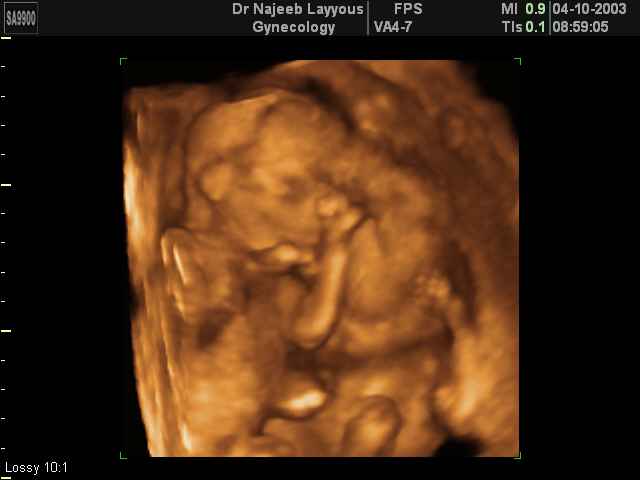

3D Photos échographie de grossesse multiple : Jumeaux, triplés et quadruples| Dr N Layyous

3D Photos échographie de grossesse multiple